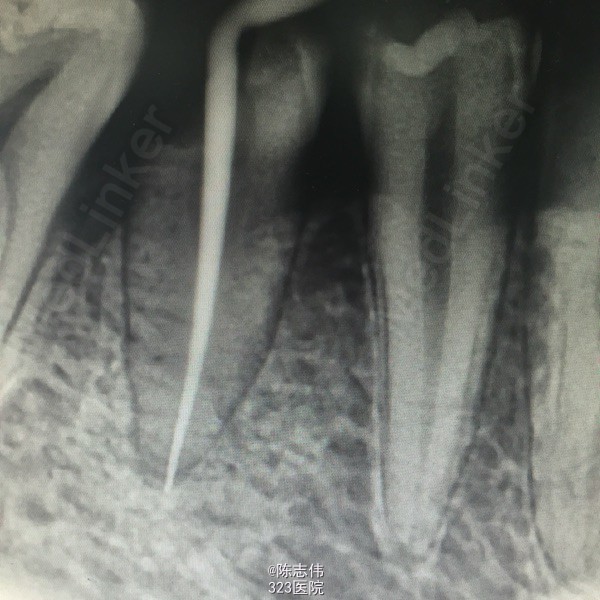

17,45RCT+桩+冠

处理:局麻下16,17,45去龋,16龋净未露髓,清理干燥隔湿后垫底+3M树脂充填。17,45揭开髓室顶,丁香油棉开放,降颌

- 王凌回复美雅:根管很漂亮

- 张景元回复宋伟颉:谢谢分享这么完整的病例!根管治疗做得很漂亮,讲解也很到位,个人觉得根管之后还是需要进行冠修复,才能保证咬合功能不受太多影响!